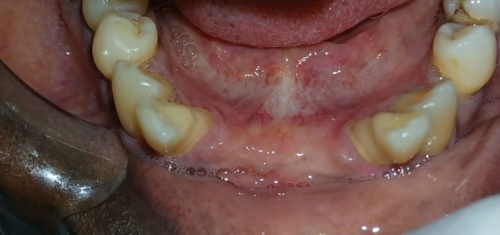

Before / After

From stained or misaligned teeth to a radiant, confident smile, our results speak for themselves. See the difference professional dental treatment can make — and imagine what we can do for you.

Teeth Cleaning (Scaling & Polishing)